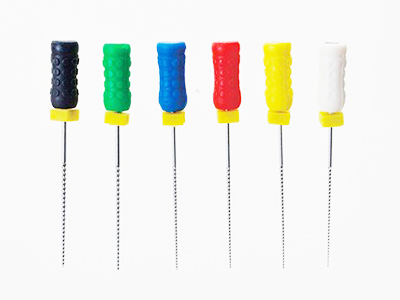

2 歯の中にある神経をファイルと呼ばれる細い器具で取り除きます(抜髄)

3 既に根管治療がしてある歯の場合には、古くなって汚れた樹脂製のお薬を取り除きます(再根管治療)

4 根管の中を徹底的に清掃・消毒し、バクテリアや腐敗した歯髄組織を取り除いてきれいにします